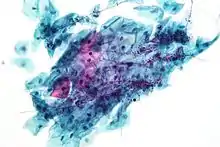

Squamous metaplasia of the cervix, with typical features. Pap stain.

Pap tests commonly examine epithelial abnormalities, such as metaplasia, dysplasia, or borderline changes, all of which may be indicative of CIN. Nuclei will stain dark blue, squamous cells will stain green and keratinised cells will stain pink/ orange. Koilocytes may be observed where there is some dyskaryosis (of epithelium). The nucleus in koilocytes is typically irregular, indicating possible cause for concern; requiring further confirmatory screens and tests.